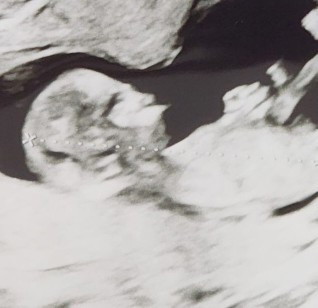

ภาพอัลตร้าซาวตอน 3 เดือน แม่ๆท่านใดซาวน์น้องละปากเป็นแบบนี้ไหมคะ ปกติไหมคะ

ปกติค่ะอาจจะยังไม่ชัดน้า รออีกสักหน่อยนะคะ น้องยังเล็กอยู่

ด้านข้างมั้ยคะภาพนี้

ด้านข้างค่ะ